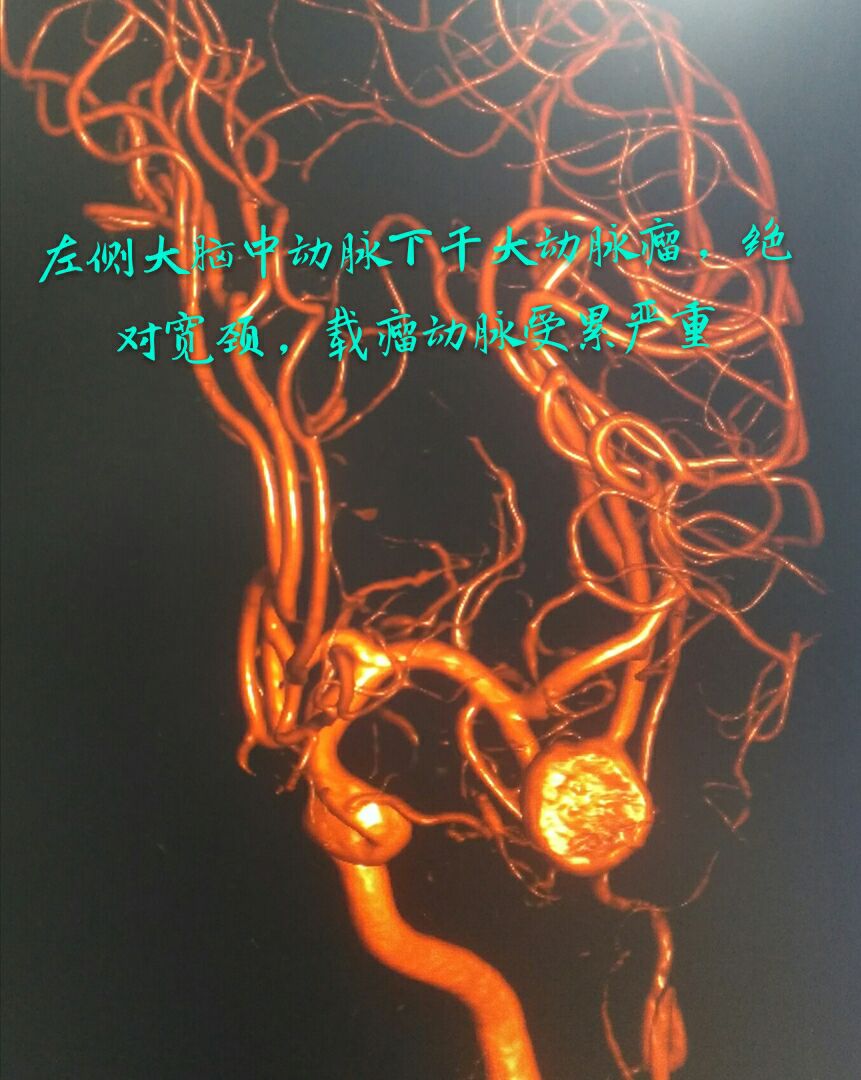

病例四:80岁男性患者,主症:头痛、脑鸣2年,DSA示左侧大脑中动脉下干大动脉瘤,绝对宽颈,载瘤动脉累及程度重

因栓塞难度大,术前做了详细、精准的计划

最准致密栓塞动脉瘤,载瘤动脉完美塑型并受到保护,难点:瘤颈极宽,辅助支架导管通过动脉瘤到达远端困难,最准微导管塑型成大弯,微导丝成袢通过动脉瘤到达远端,成功释放支架,动脉瘤栓塞后患者头痛、脑鸣症状消失